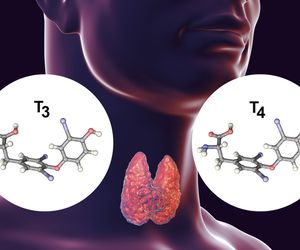

W ciele człowieka funkcjonuje kilkanaście gruczołów dokrewnych wśród których można wymienić m.in. szyszynkę, tarczycę, wątrobę i trzustkę. Na cały układ hormonalny składa się kilkadziesiąt różnych hormonów, które pozostają ze sobą w stałej równowadze.

Do typowych zaburzeń hormonalnych można zaliczyć m.in. chorobę Cushinga, PCOS, choroba Hashimoto oraz niedoczynność lub nadczynność tarczycy. Każdą z tych jednostek leczy się inaczej, w zależności od ogólnego stanu zdrowia pacjenta.